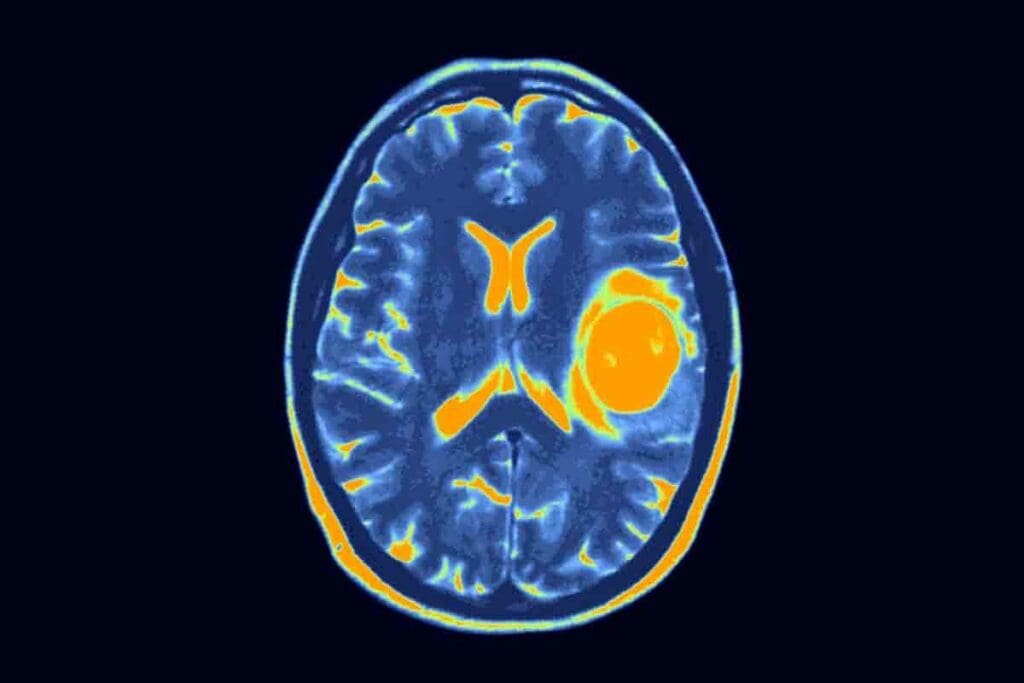

Advanced Imaging Techniques

Advanced imaging is vital for diagnosing glioblastoma multiforme. Magnetic Resonance Imaging (MRI) is the main tool used. MRI gives clear brain images, showing the tumor’s size and its effect on the brain.

At times, Computed Tomography (CT) scans or Positron Emission Tomography (PET) scans are also used to get more details.